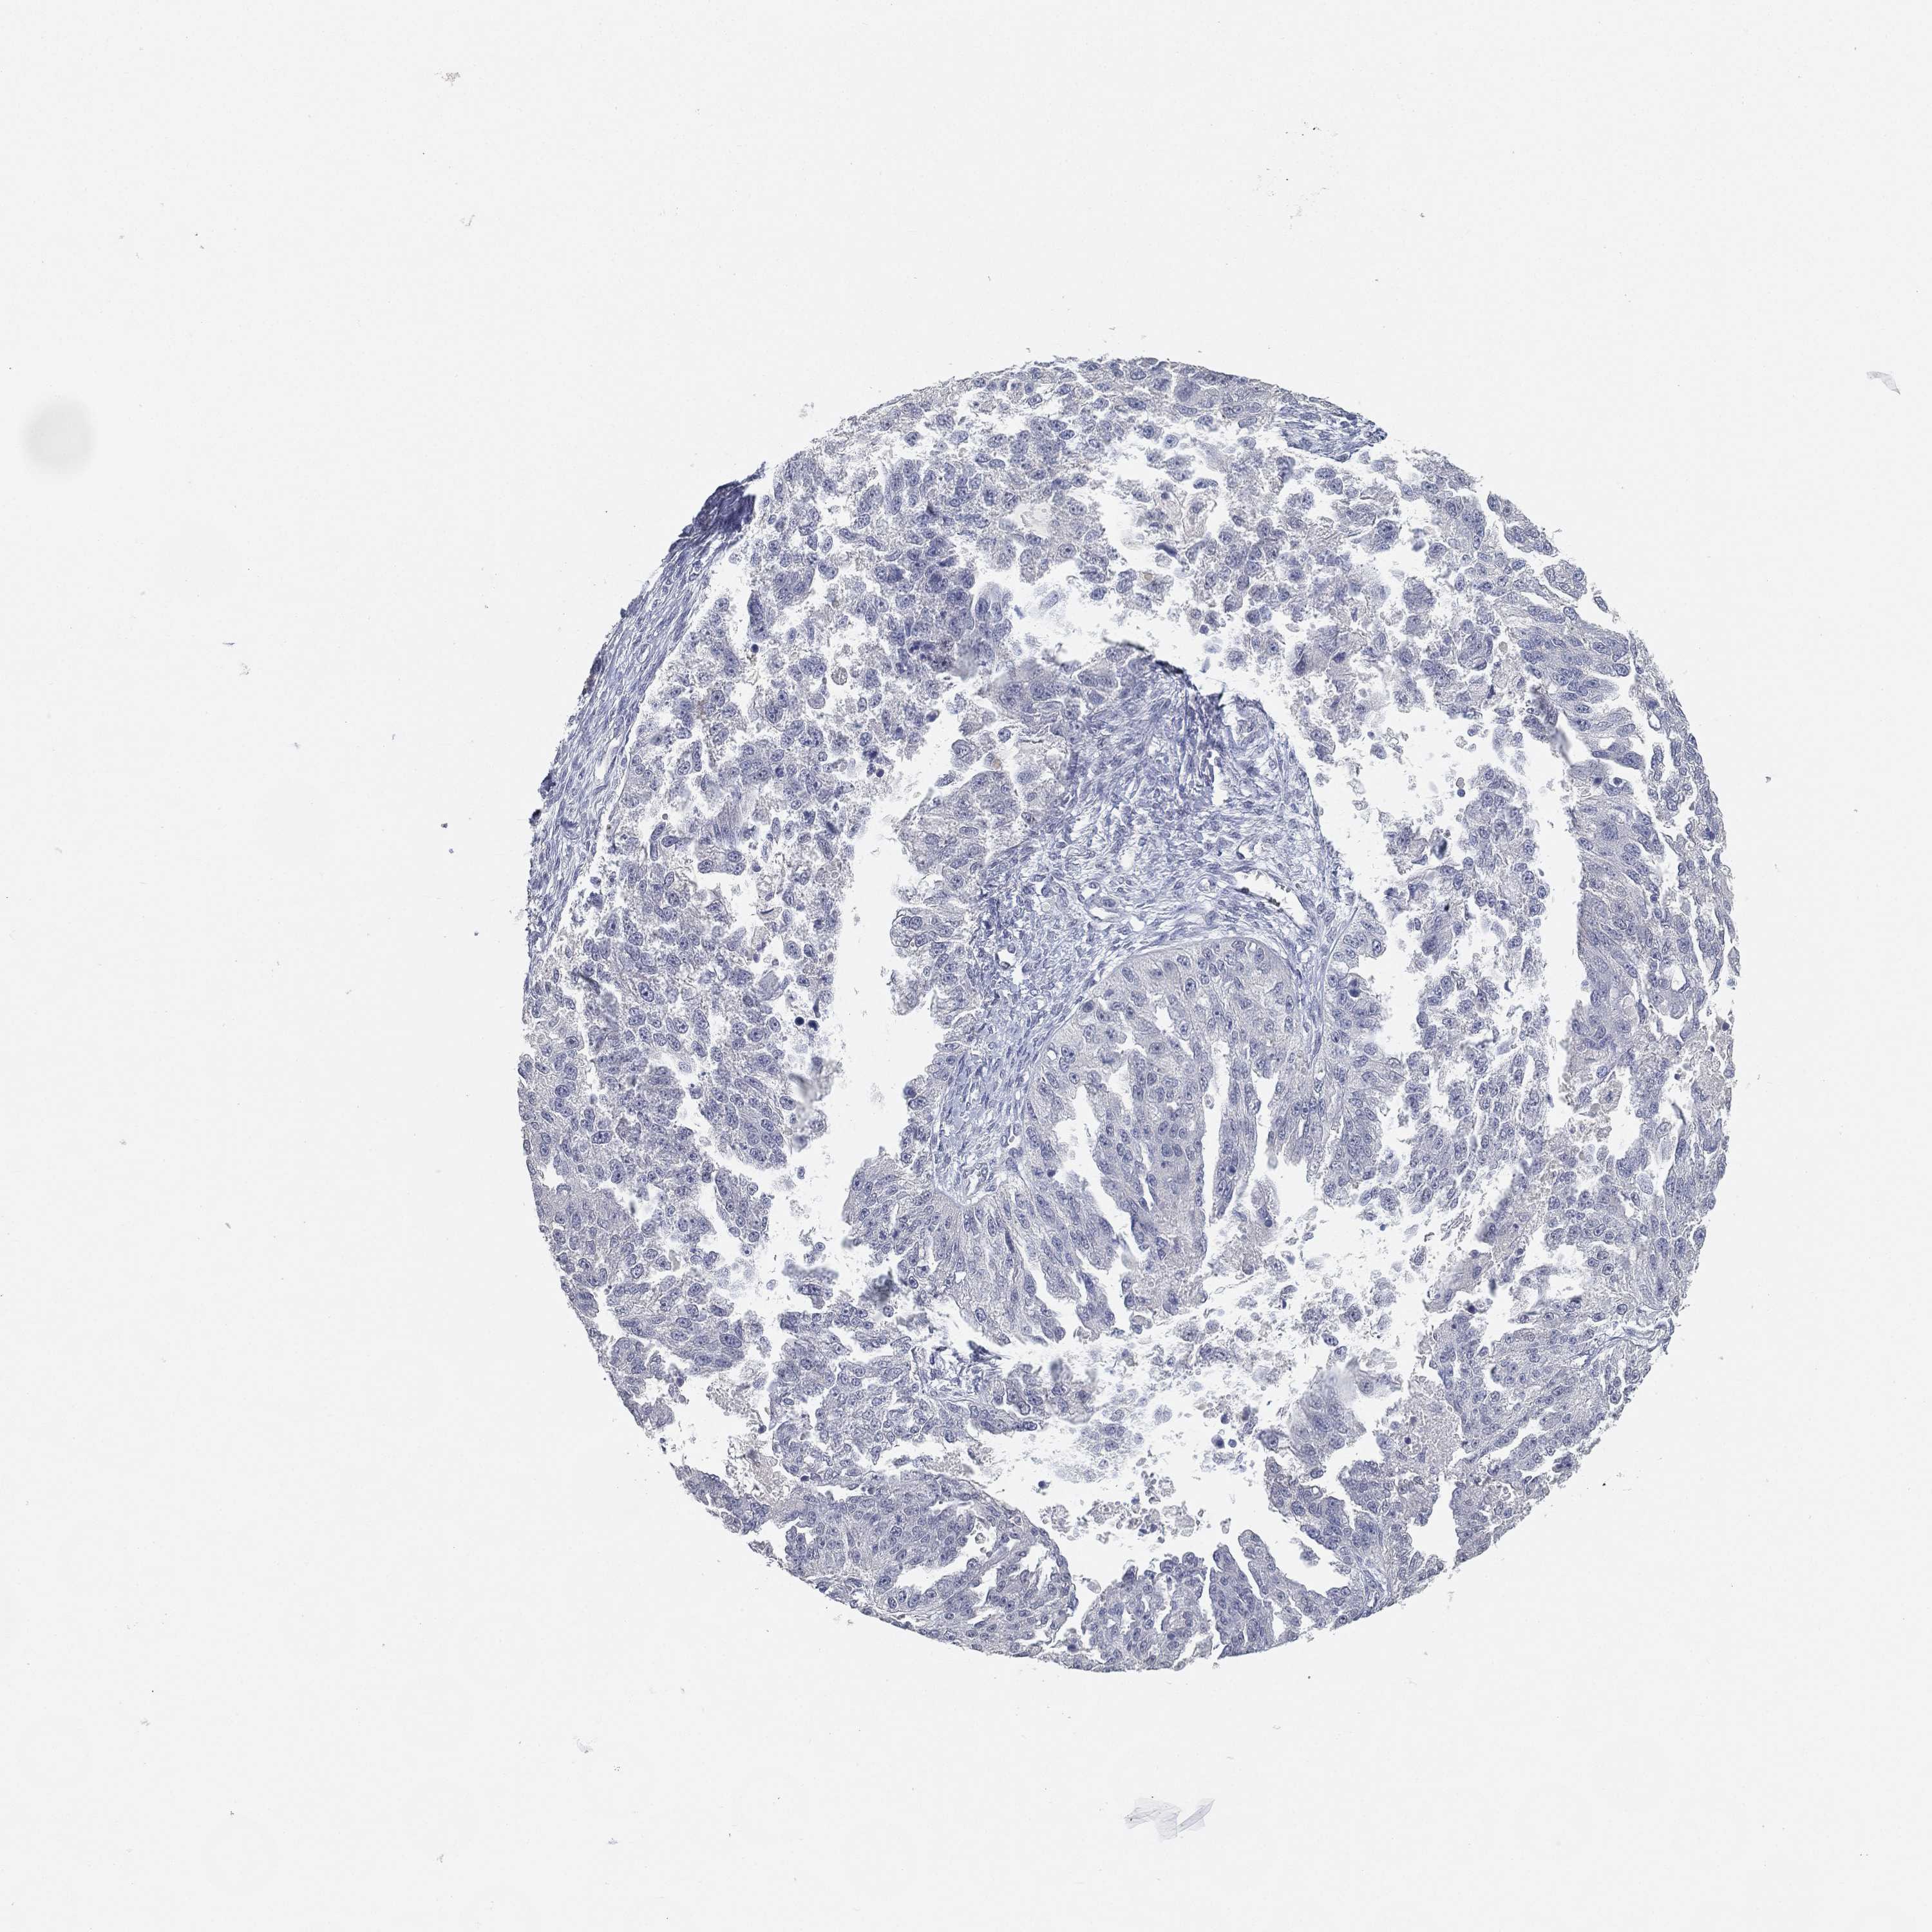

OVARIAN CANCER - Protein expressioni

A mouse-over function shows sample information and annotation data. Click on an image to view it in a full screen mode. Samples can be filtered based on level of antibody staining by selecting one or several of the following categories: high, medium, low and not detected. The assay and annotation is described here.

Note that samples used for immunohistochemistry by the Human Protein Atlas do not correspond to samples in the TCGA dataset.

Antibody stainingi

Antibody staining in the annotated cell types in the current human tissue is reported as not detected, low, medium, or high, based on conventional immunohistochemistry profiling in selected tissues. This score is based on the combination of the staining intensity and fraction of stained cells.

Each image is clickable and will lead to virtual microscopy that enables deeper exploration of all samples and also displays staining intensity scores, fraction scores and subcellular localization as well as patient and tissue information for each sample.

Antibody HPA007326

Antibody HPA026088

Cystadenocarcinoma, serous, NOS

Cystadenocarcinoma, mucinous, NOS

Carcinoma, endometroid